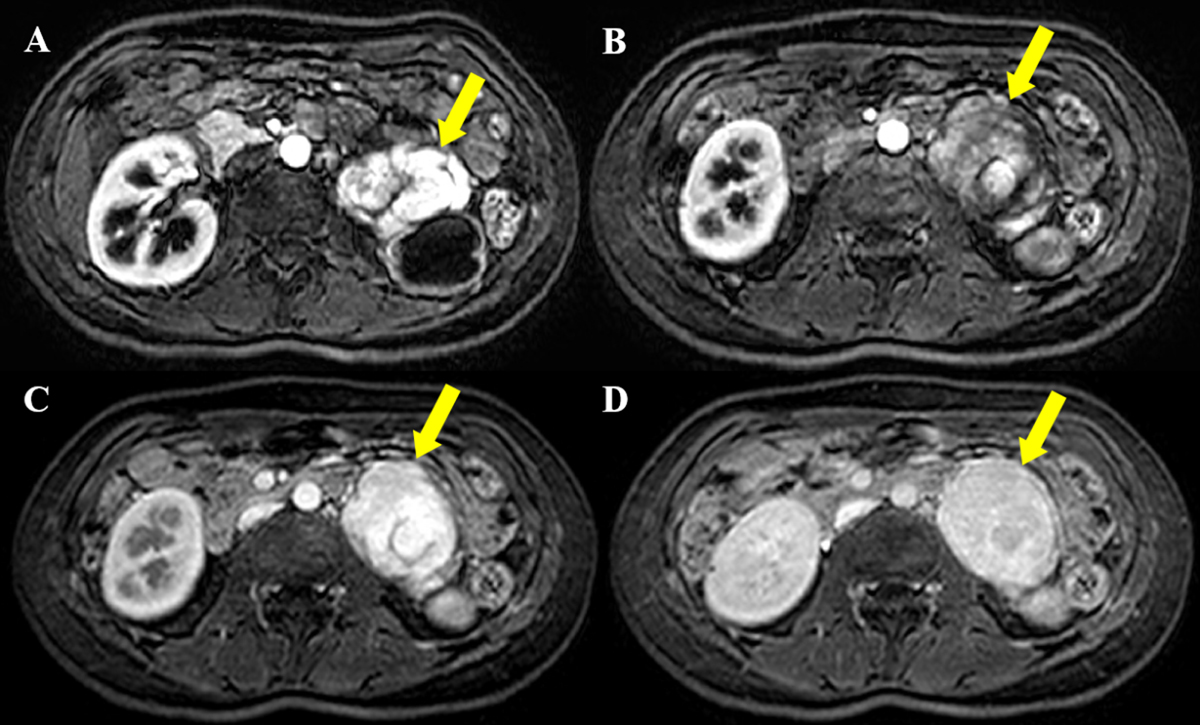

A 30-year-old female was admitted to our hospital after an elevated carbohydrate antigen (CA 19-9, 42.1 U/ml) was discovered on a health check-up. Her past medical history was unremarkable. Contrast-enhanced computed tomography (CT) was performed to check for abdominal malignancy. Axial and coronal reformatted arterial phase CT images (Figure 1A, B, C) showed an 8 cm, avidly heterogeneous enhancing mass (arrow) below the left kidney (open arrow). Left hydronephrosis (open arrow) occurred as the mass (arrow) compressed the left upper ureter. Coronal maximum-intensity projection reformatted CT image (Figure 1D) revealed multiple serpentine arteries (open arrowheads) along the periphery of the mass (arrow). The patient underwent magnetic resonance imaging (MRI) for further evaluation. The retroperitoneal mass (arrow) was iso-intense on T1-weighted image and hyperintense on T2-weighted image, with a well-circumscribed margin (Figure 2A and 2B). Coronal T2-weighted image revealed multiple signal voids (open arrowheads) along the periphery of the mass (arrow), a finding that suggests the vessels (Figure 2C). Axial dynamic gadolinium-enhanced T1-weighted images demonstrated the mass (arrow) with heterogeneous and strong enhancement on the arterial phase (Figure 3A and 3B) and prolonged enhancement on the portal venous and three-minute delayed phase (Figure 3C and 3D). The patient underwent mass excision and left nephrectomy, and she was diagnosed with retroperitoneal solitary fibrous tumor (SFT).

Figure 3